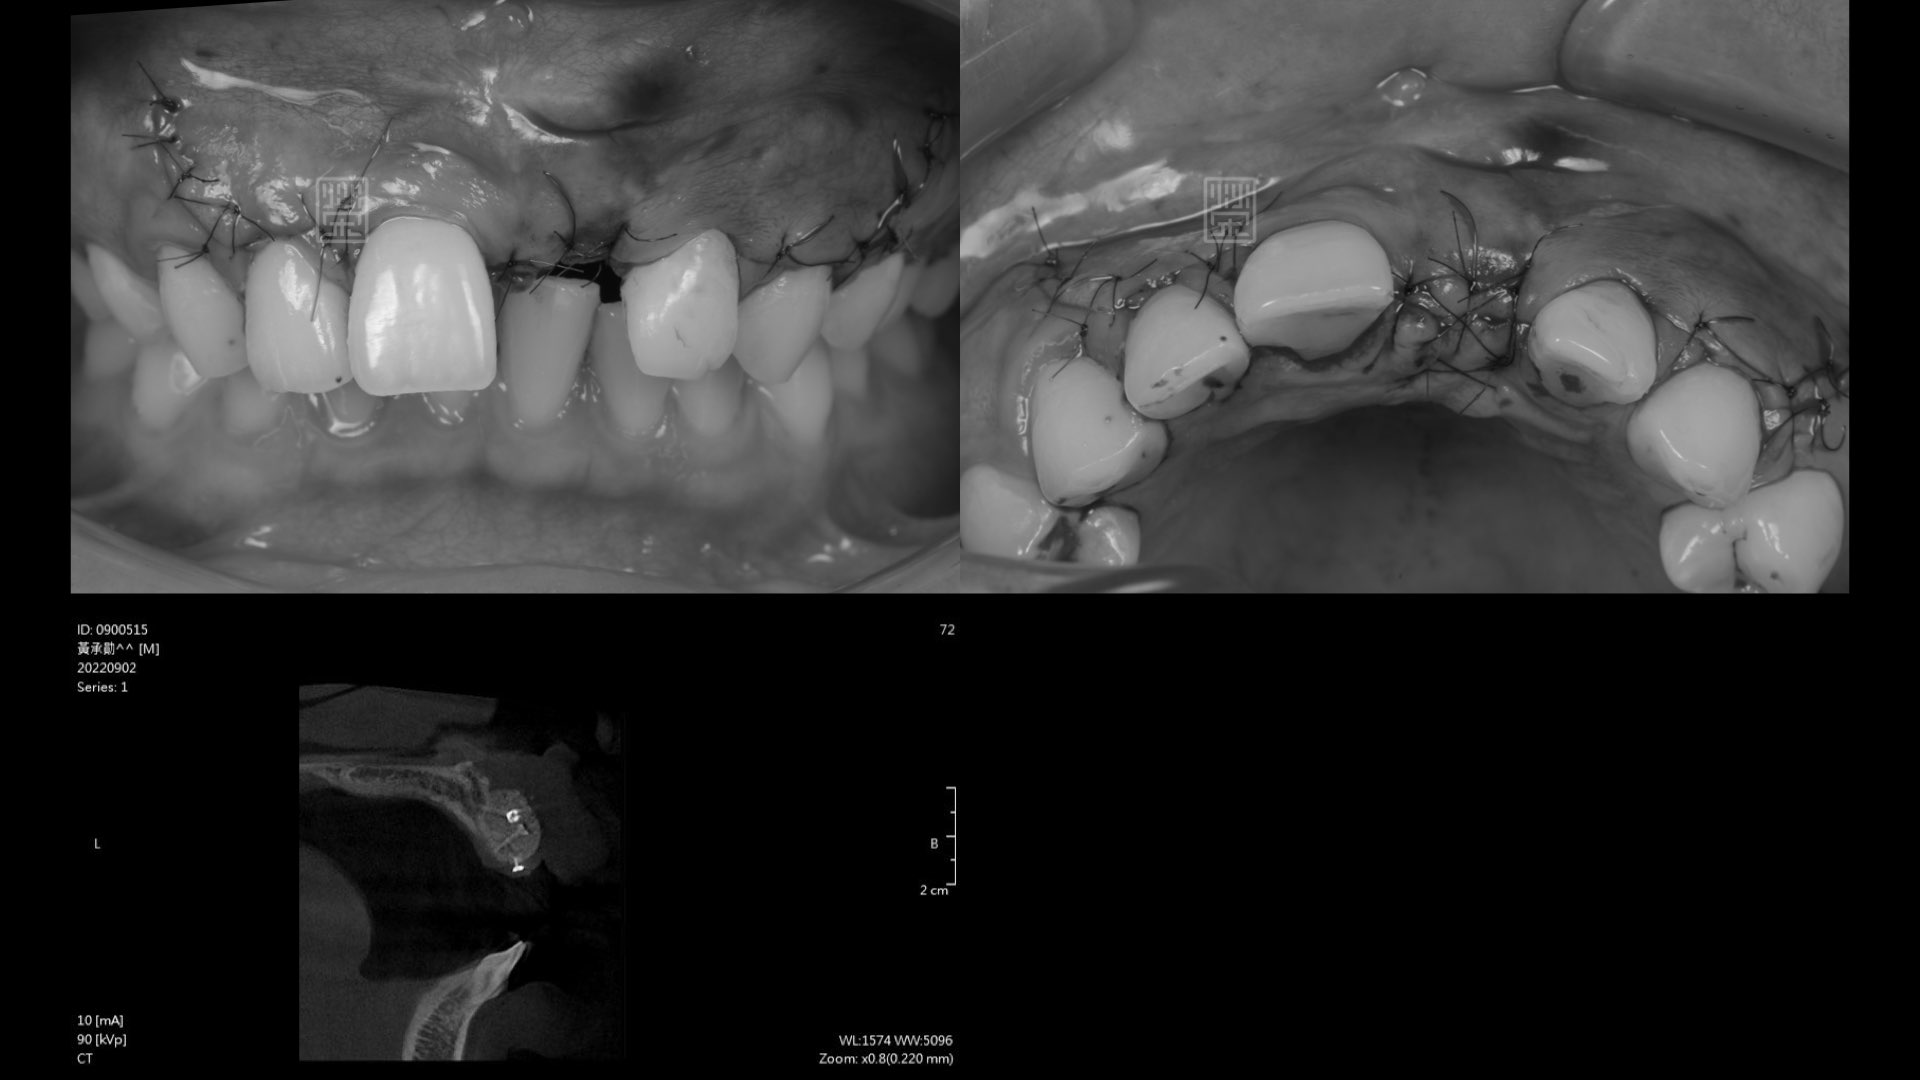

初次補骨

植牙與再次補骨

牙齦軟組織重建